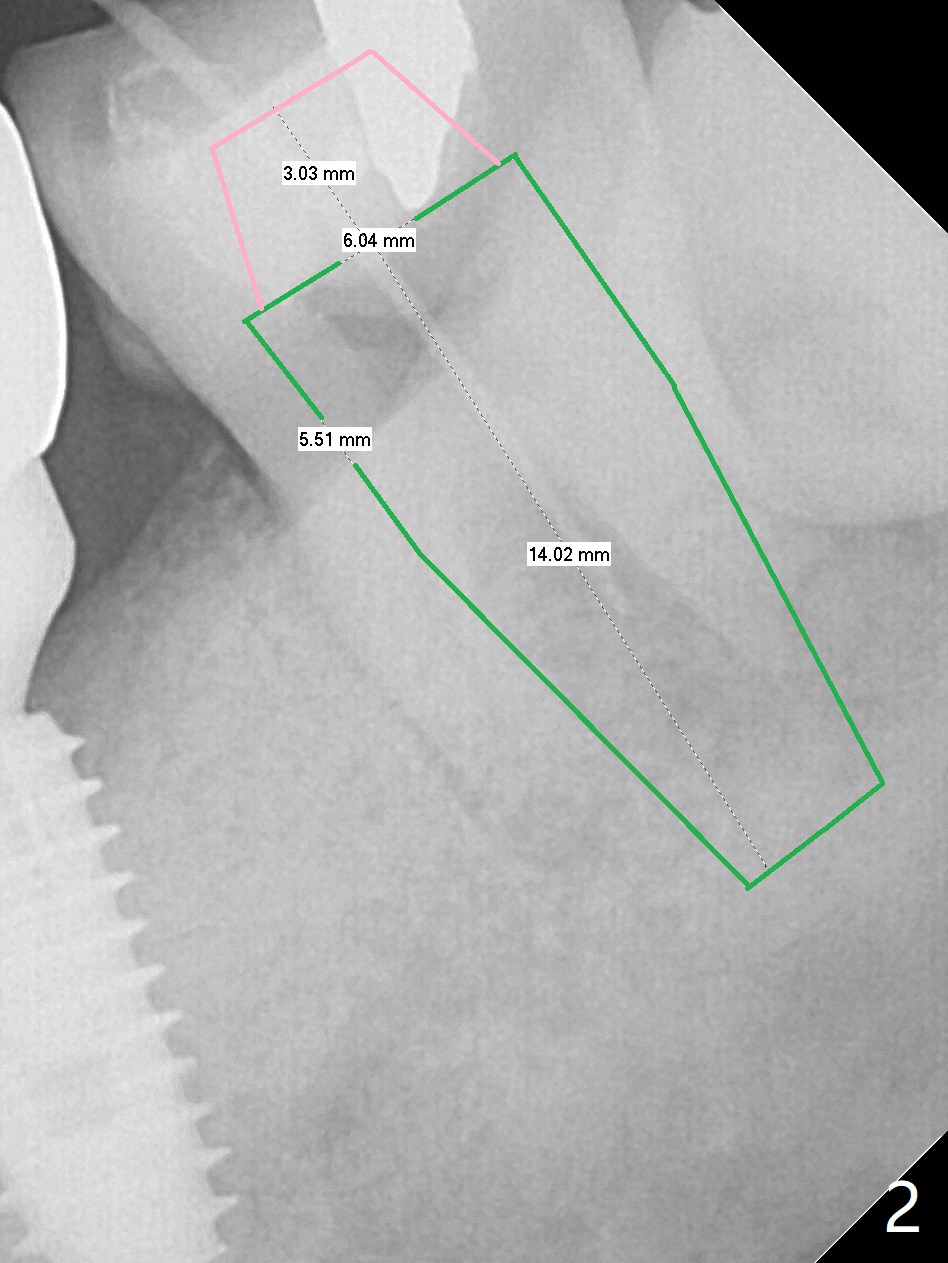

A 58-year-old man appears to have furca lesion or fracture the roots of the tooth #18 three years 5 months post cementation of #19 (Fig.1). In fact the abutment screw gets loose twice even with a buried screw driver. The implant at #18 will be a large tissue-level one (Fig.2). Use a thumb driver to place the implant initially through the metal sleeve for orientation. Although bone resorption mesial to #19 implant looks more severe in panoramic X-ray (Fig.3 *) and the sagittal view of CT (Fig.5) than PA (Fig.1), there is bone (less density) buccal (B) and lingual (Fig.5 *). Bone graft will be conducted at #19 if clinical exam confirms deep pocket the same time of #18 surgery. Distal radiolucency of #18 (Fig.3 *) makes it necessary to extract #17 simultaneously as well. Prepare Titanium brush.